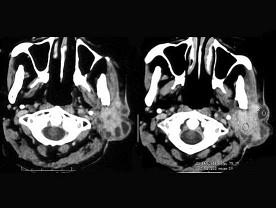

问题 女,55岁,鼻咽癌放疗15年,近一周左耳根部肿胀,无发热,PE:左耳根部皮下扪及三个结节,有波动感和轻压痛,CT如图所示,最可能的诊断是 ( )

选项 A、左腮腺恶性混合瘤 B、左腮腺蜂窝织炎 C、左腮腺混合瘤 D、左腮腺腺淋巴瘤 E、左腮腺腺瘤

答案 B